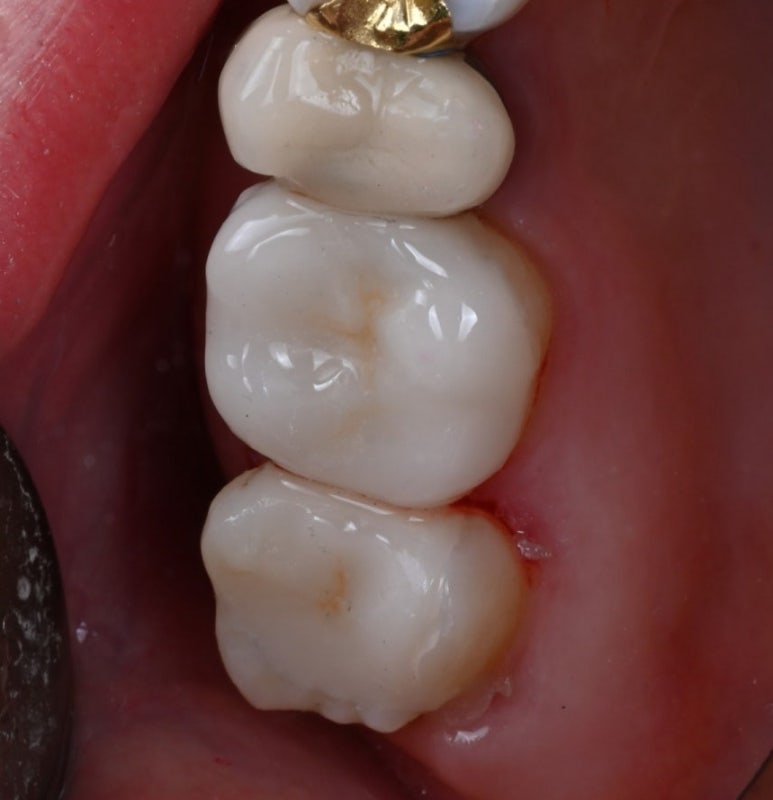

25.11.19 접착 후

25.11.19 교합조정까지 마친 후

환자분께서는 자기 치아처럼

자연스러워진 모습에 매우 만족해하셨습니다.

치료 후 현재까지 별다른 불편함 없이

아주 잘 사용하고 계신다는 소식을 전해주셨습니다.